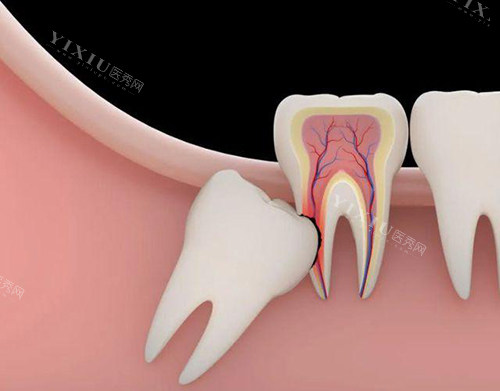

拔智齿

神木海涛口腔的拔智齿价格如下:

| 拔牙类型 | 价格区间(元) |

|---|---|

| 普通智齿拔除 | 280起 |

| 复杂阻生智齿 | 2000起 |